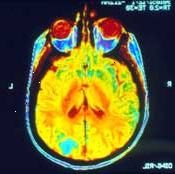

Μαγνητική τομογραφία (MRI)

Μια μαγνητική τομογραφία μπορεί να χρησιμοποιηθεί για να καθοριστεί εάν ο καρκίνος έχει εξαπλωθεί στο στήθος ή τον εγκέφαλο σας. Εάν έχει, ένα MRI μπορεί επίσης να δείξει το μέγεθος και την έκταση της εξάπλωσης. Ο γιατρός σας μπορεί επίσης να ζητήσει μια μαγνητική τομογραφία, εάν τα αποτελέσματα της μια ακτινογραφία ή αξονική τομογραφία δεν δίνουν σαφώς την απάντηση. Σε ορισμένες περιπτώσεις, θα είναι ένεση με σκιαγραφικό λίγο πριν πάρει τη σάρωση. Για τη δοκιμή αυτή, θα βρίσκονται ακόμα σε ένα τραπέζι καθώς περνά μέσα από ένα σαρωτή. Ένας υπολογιστής χρησιμοποιεί τα δεδομένα από τα μαγνητικά κύματα για να δημιουργήσει πολύ λεπτομερείς εικόνες από το εσωτερικό του σώματός σας. Κάθε εικόνα μπορεί να χρειαστούν 2 έως 15 λεπτά, έτσι ώστε η όλη εμπειρία μπορεί να διαρκέσει μία ώρα ή περισσότερο. Αυτές οι εικόνες μπορούν να δείχνουν τη διαφορά μεταξύ κανονικών και παθολογικού ιστού. Αυτή η μέτρηση είναι ανώδυνη. Ρωτήστε για ωτοασπίδες δεδομένου ότι υπάρχει ένας δυνατός υπόκωφος θόρυβος κατά τη σάρωση. Εάν είστε κλειστοφοβικός, μπορεί να χρειαστεί ένα ηρεμιστικό πριν από αυτή τη δοκιμασία.